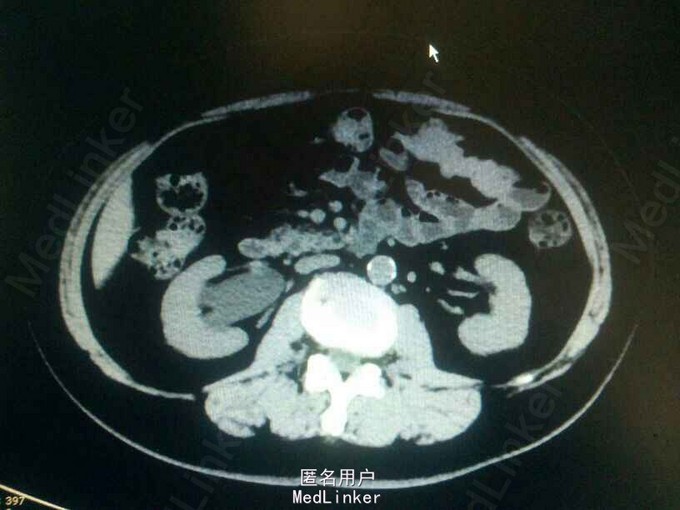

查体:无明显阳性体征! 辅助检查:CTU提示:右侧输尿管下段占位?输尿管镜检,右侧输尿管下段新生物,约1*1cm,病检示高级别浸润性尿路上皮癌?

右侧输尿管下段癌